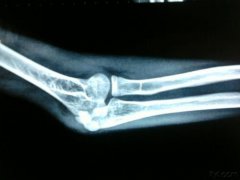

什么是肘管综合征?

哪些原因会引起肘管综合征呢

肘管综合征有什么症状?怎么治疗好

肘管综合征怎么治疗?什么时候治疗好呢